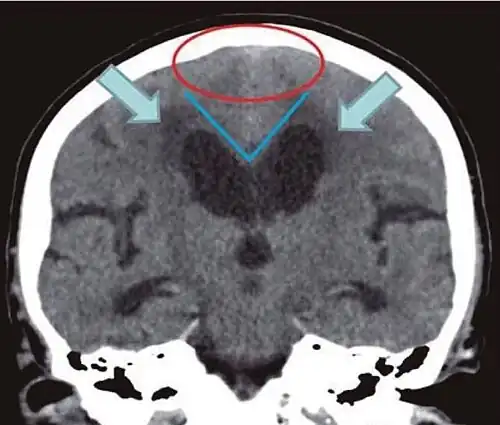

- Imaging from magnetic resonance imaging (MRI) or computed tomography (CT) is needed to demonstrate enlarged ventricles and no macroscopic obstruction to cerebrospinal fluid flow. Imaging should show an enlargement to at least one of the temporal horns of lateral ventricles, and impingement against the falx cerebri resulting in a callosal angle ≤ 90° on the coronal view, showing evidence of altered brain water content, or normal active flow (which is referred to as "flow void") at the cerebral aqueduct and fourth ventricle.

Normal pressure hydrocephalus | Brain atrophy | |

Preferable projection | Coronal plane at the level of the posterior commissure of the brain. | |

Modality in this example | CT | MRI |

CSF spaces over the convexity near the vertex (red ellipse ![]() |

Narrowed convexity ("tight convexity") as well as medial cisterns | Widened vertex (red arrow) and medial cisterns (green arrow) |

Callosal angle (blue V) | Acute angle | Obtuse angle |

Most likely cause of leucoaraiosis (periventricular signal alterations, blue arrows ![]() |

Transependymal cerebrospinal fluid diapedesis | Vascular encephalopathy, in this case suggested by unilateral occurrence |

MRI scans are the preferred imaging. The distinction between normal and enlarged ventricular size by cerebral atrophy is difficult to ascertain. Up to 80% of cases are unrecognized and untreated due to difficulty of diagnosis.[22] Imaging should also reveal the absence of any cerebral mass lesions or any signs of obstructions. Although all patients with NPH have enlarged ventricles, not all elderly patients with enlarged ventricles have primary NPH. Cerebral atrophy can cause enlarged ventricles, as well, and is referred to as hydrocephalus ex vacuo. For these reasons it's utmost important to note that Evan's index although commonly used in imaging is not very specific for NPH. One recent systematic review and meta-analysis suggests that callosal angle has high diagnostic performance and is commonly used together with Evan's index.[23]